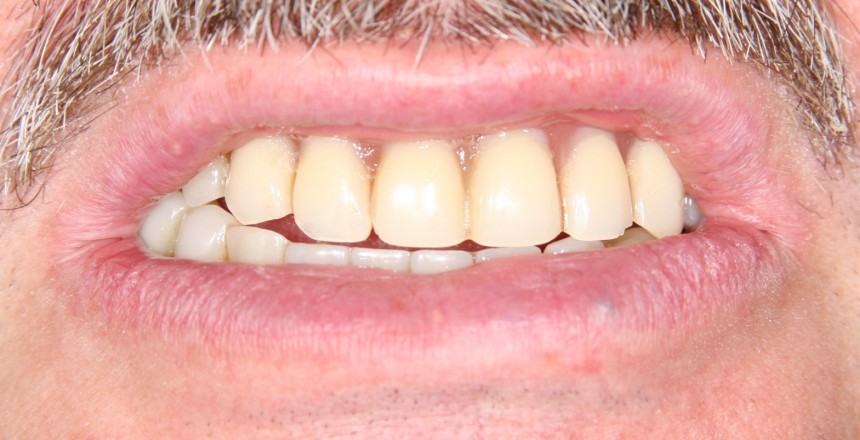

Насколько правдива реклама и отзывы о базальной имплантации? Можно ли им верить? Вот картинки с сайта клиники, которая активно занимается базальной имплантации, я взял одну из их работ. Кому интересно, можно погуглить. Там их очень много, с описанием.

Что отличает все эти демонстрации от того, что мы видим у умных докторов? Ни один из снимков не показывает состояние десны вокруг имплантов (а это, между прочим, является важным критерием качества лечения), все розовое, что вы видите на снимке — это искусственная керамическая или пластмассовая десна. С таким же успехом можно просто удалить пациенту все зубы, поставить съемный протез и сделать фотку. И будет все отлично смотреться. Вот, к примеру, мой пациент, который носит временный съемный протез и готовится к нормальной имплантации: